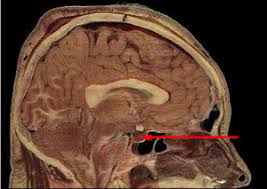

Dabei wird die Hypophyse als Ausführungsorgan bezeichnet denn diese übernimmt die Rolle der Freisetzung. Trotz ihrer Größe ist sie eine äußerst wichtige Drüse. Die Hypophyse befindet sich unter dem Gehirn und ist eine erbsengroße endokrine Drüse die in einer knöchernen Tasche in der Schädelbasis sitzt die als Hypophysenfossa bezeichnet wirdDie Hypophysenfossa ist auch als Sella Turcica bekannt was übersetzt türkischer Sattel bedeutet da sie einem Sattel mit Stützen vorne und hinten ähnelt die vom türkischen Volk.

Sie bilden das kleine Machtzentrum in unserem Gehirn das Descartes als Sitz unserer Seele definierte. Der griechische Name Hypophyse bedeutet wörtlich das unten anhängende Gewächs. Die Hypophyse steuert die Funktion der meisten Drüsen die ihre. Die Hypophyse selbst ist nur so groß wie ein Kirschkern und besteht aus zwei Teilen mit unterschiedlicher Funktion. Hypophyse Hormondrüse im Türkensattel. Die Hypophyse ist eine winzige Drüse nicht größer als eine Erbse die sich an der Unterseite des Gehirns befindet. Trotz ihrer Größe ist sie eine äußerst wichtige Drüse. Wenn Tumoren auf die Hypophyse drücken stören sie die Hormonbildung. Sie sitzt auf der Sella turcica Türkensattel einer Vertiefung der Schädelbasis mitten in unserem Schädel etwa auf Höhe der Nase und der Ohren.